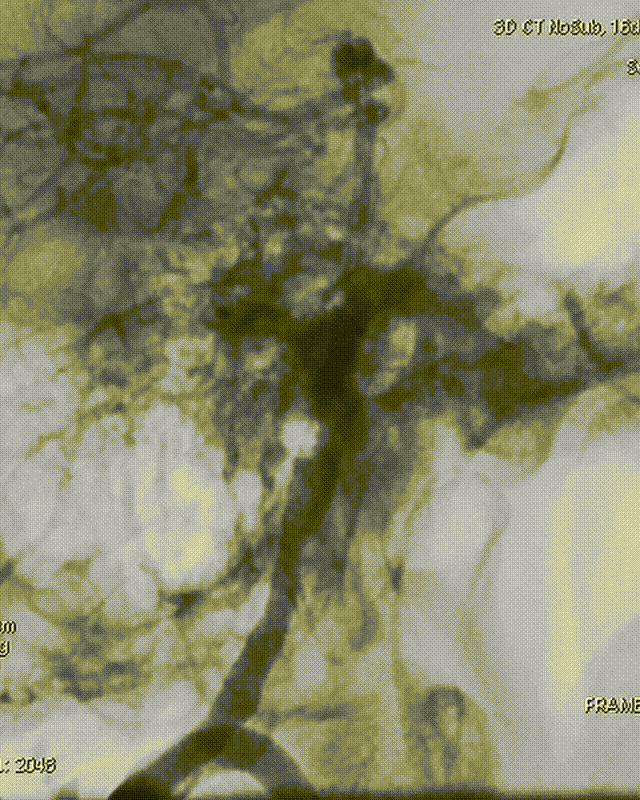

Roadmap

通桥白驹®球囊(2.5*10),先远后近扩张。

球扩后,狭窄改善。